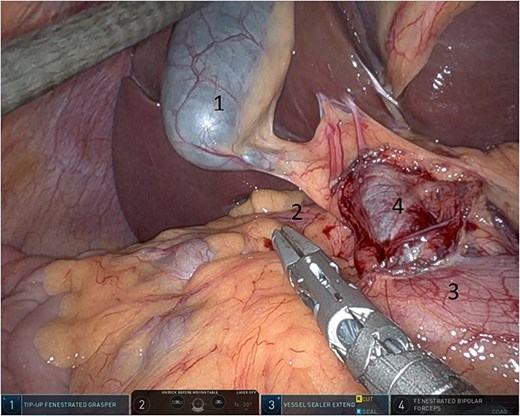

Upon entering the abdominal cavity, dilated bowel loops were observed (Fig. 2), and a significant portion of the colon was found herniated through the foramen of Winslow (Fig. 3). The herniated colon was covered by the pars flaccida (Fig. 4) (Video S1). Careful dissection was performed anterior to the hepatoduodenal ligament (Fig. 5). The gall bladder was retracted to the patient's right upper quadrant, which allowed for the retraction of the foramen of Winslow (Fig. 6) (Video S1). After carefully placing the tip of the instrument posterior to the portal vein and gently elevating it, the herniated colon was successfully reduced (Fig. 7) (Video S1).

Gallbladder was retracted to the patient's right upper quadrant which allowed for the retraction of the foramen of Winslow and anterior mobilization of it (1: gall bladder, 2: herniating colon, 3: first part of the duodenum, 4: portal vein).